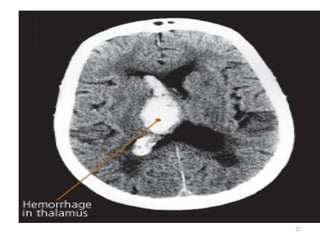

Cerebrovascular Accident

Hemorrhage Stroke

Intracerebral Hemorrhage

 Rupture of a vessel

 Hypertension – most important cause

 Others: vascular malformations, coagulation disorders,

anticoagulation, trauma, brain tumor, ruptured aneurysms

 Sudden onset of symptoms with progression

 Neurological deficits, headache, nausea, vomiting, decreased

LOC, and hypertension

 Prognosis: poor – 50% die within weeks

 20% functionally independent at 6 months

21